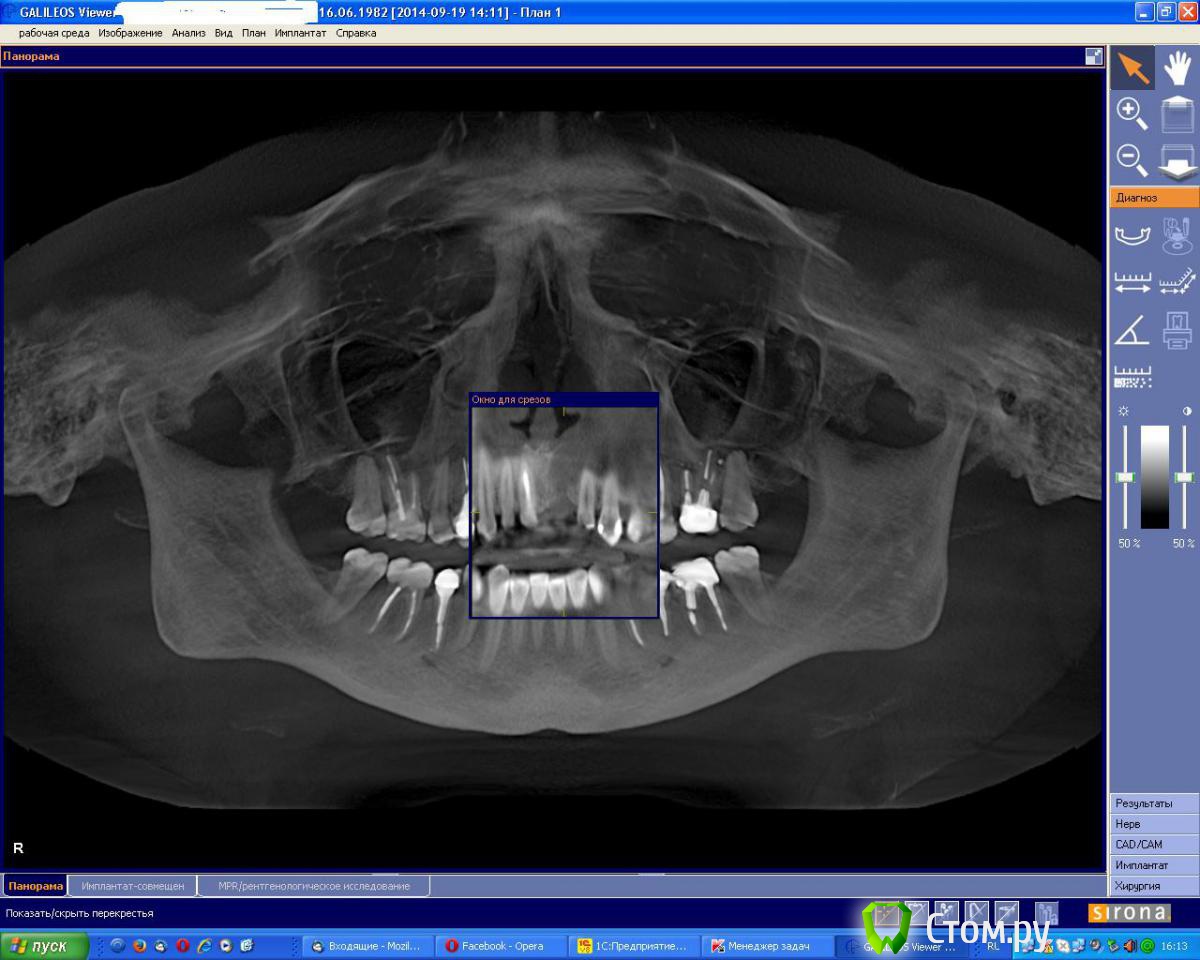

an_ver Опубликовано 19 сентября, 2014 Поделиться Опубликовано 19 сентября, 2014 (изменено) Молодая девушка,ранее был удален 21..с ее слов после удаления началось воспаление,выводили 2 месяца.После удаления-выведения прошло 6 месяцев. Сейчас фиксирован адгезивный мост. Вот такую картину имеем на сегодня. Что посоветуете,коллеги.Девушка хочет зуб Изменено 19 сентября, 2014 пользователем an_ver Ссылка на комментарий

zzkz Опубликовано 19 сентября, 2014 Поделиться Опубликовано 19 сентября, 2014 Почистил и сделал бы МПК, пики позволяют, с ССТ или ВИП. Если слизистой мало совсем. Ссылка на комментарий

Alexey Doc Опубликовано 19 сентября, 2014 Поделиться Опубликовано 19 сентября, 2014 Почистил и сделал бы МПК, пики позволяют, с ССТ или ВИП. Если слизистой мало совсем. +1 подойдет любой каркасный метод (каким лучше владеете) + работа со слизистой Ссылка на комментарий

faity Опубликовано 19 сентября, 2014 Поделиться Опубликовано 19 сентября, 2014 этож 3-х стеночный дефект, можно при желании НРТ обойтись Ссылка на комментарий

an_ver Опубликовано 2 октября, 2014 Автор Поделиться Опубликовано 2 октября, 2014 Пики есть, уровень тоже. Согласен с Alexey Dok и faity, тут любая техника сработает от мембранной до ламината. Если эстетика немаловажна - VIP-CT или чего попроще.VIP на графт,сверху мембрану? Ссылка на комментарий